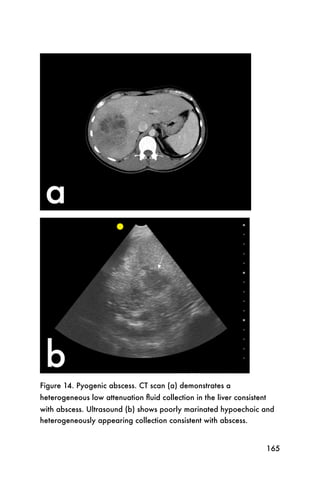

cholecystitis are usually unable to eat large meals before

presenting for evaluation due to pain. The contracted

gallbladder is usually difficult to localize and the wall

will appear thickened. A contracted gallbladder is